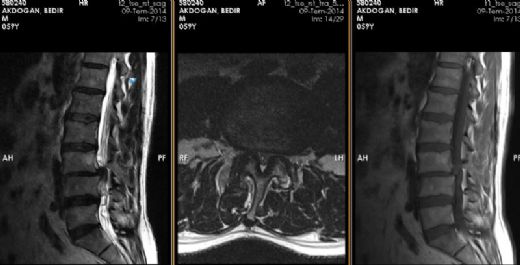

Bel Fıtığı ve Platin Takılması: Genel BilgilerBel fıtığı, omurganın aşağı kısmında yer alan disklerin (intervertebral disklerin) yıpranması sonucunda oluşan bir rahatsızlıktır. Bu durum, diskin içindeki jel benzeri maddelerin dışarı çıkması ve sinirlere baskı yapmasıyla karakterizedir. Bel fıtığı, sırt ağrısı, bacaklarda uyuşma, güçsüzlük ve hareket kısıtlılığı gibi belirtilerle kendini gösterir. Platin Takılması: Neden ve Nasıl Uygulanır? Bel fıtığı tedavisinde, cerrahi müdahaleler gerekebilir. Bu tür durumlarda, omurga stabilitesini sağlamak amacıyla platin (metal veya biyomateryal) takılması tercih edilebilir. Platin, omurga yapılarını bir arada tutarak iyileşme sürecine destek olur. Platin Takılmasının Zararları Platin takılmasının bazı potansiyel zararları ve komplikasyonları şunlardır:

Bel Fıtığı ve Platin Takılması